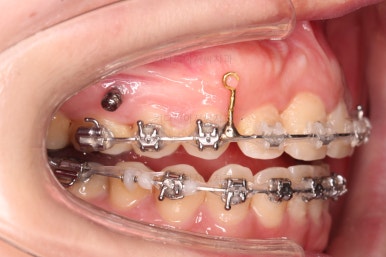

미니스크류를 적절히 사용해서 부정교합도 맞추고 입매도 약간 들어가게 혹은 너무 들어가지 않게 조절해 주고요.

치열의 경사 등등도 조절해 줍니다.

부산부정교합이긴 하지만 애초에 입매가 많이 나쁘진 않았기 때문에 자칫하면 입이 너무 들어갈 수 있어 중간중간 환자분과 상의하여 너무 들어가지 않게끔 조절해 줍니다.

적절하게 틈도 다 모아주고요.

디테일을 정리하고 마무리를 하게 됩니다.